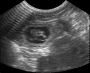

על מסך הסורק נראו גורים בגודל של כ-6 מ"מ כשיחד עם השק גודלם הכולל היה כשני ס"מ. הצלחנו אפילו לתפוס בתמונה דופק של אחד הגורים - מראה מרגש במיוחד עבורי שזו הפעם הראשונה שאני רואה דופק בגורים של כלבה שלי. זו סה"כ גם הפעם הראשונה שאני עושה את הבדיקה הזו, הסיבה העיקרית היא שאינני משלמת עליה כסטודנטית וכי אתם קוראי היומן בטוח שמחים לראות את התמונות.

אז זהו להיום, אני מצרפת תמונה של קסם מתאמול בפרופיל שכן כבר ניתן להתחיל ולהבחין בבטן שאיננה משוכה כמו תמיד ותמונות של הסריקה עצמה ומהסריקה עם כל הסקרנים מסביב. למי מכם שעוד לא ראה תמונות מאולטרא סאונד ואינו יודע להבחין, חפשו בתמונות מאין כדורים עם גבול בגוון לבן ותכולה שחורה עם כתם לבן. הגבול הלבן הוא השק, התכולה השחורה הם הנוזלים המקיפים את העובר והכתם הלבן הוא העובר.